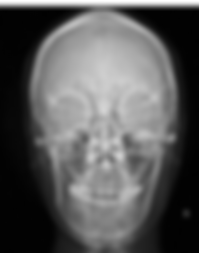

Radiografia Frontal

Descrição: Radiografia que se propõem, sem deformação e sem aumento apreciável, fornecer uma imagem dos ossos do crânio, da face e das partes moles. Indicada para avaliar presença de anormalidades de crescimento ou assimetria da maxila ou mandíbula.

Na Perfil Radiologia, realizamos esse exame com alta resolução e padronização técnica, garantindo imagens nítidas e precisas para diagnóstico e acompanhamento clínico.

Visualização: ossos da face e crânio para avaliação do crescimento, desenvolvimento, relação esqueletal, simetria, estudos das adenóides, processos patológicos e traumáticos. ossos da face e crânio para avaliação do crescimento, desenvolvimento, relação esqueletal, simetria, estudos das adenóides, processos patológicos e traumáticos.

Utilização: Indicada para na ortodontia para avaliar: presença de anormalidades de crescimento e realização de traçados ou na prática cirúrgica para avaliar assimetria da maxila ou mandíbula.